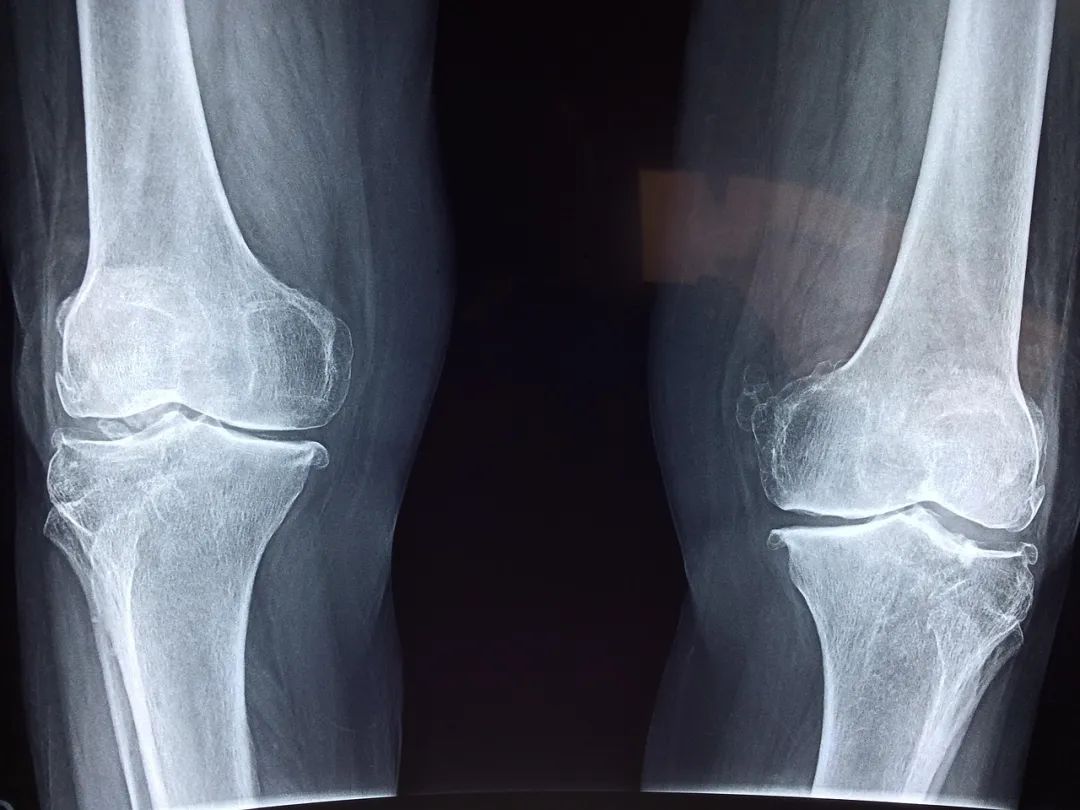

骨关节炎是一种退行性关节疾病,随着年龄的增长,关节软骨逐渐磨损,关节边缘会出现骨质增生(骨刺)。当关节活动时,磨损的软骨和增生的骨质相互摩擦,就会产生弹响,同时还可能伴有疼痛、肿胀、僵硬等症状,尤其是在活动后或长时间休息后症状会加重。